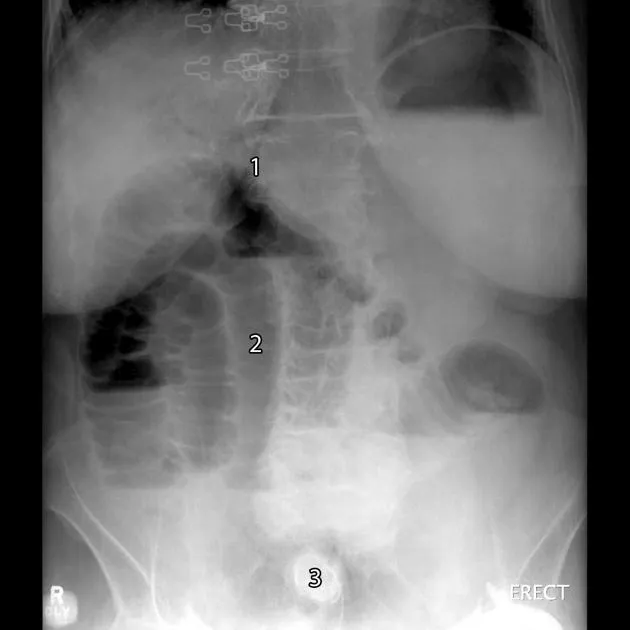

⭐ Gallstone Ileus: A classic complication where a large stone passes through a fistula and obstructs the ileocecal valve, causing Rigler's triad: pneumobilia, small bowel obstruction, and an ectopic gallstone.